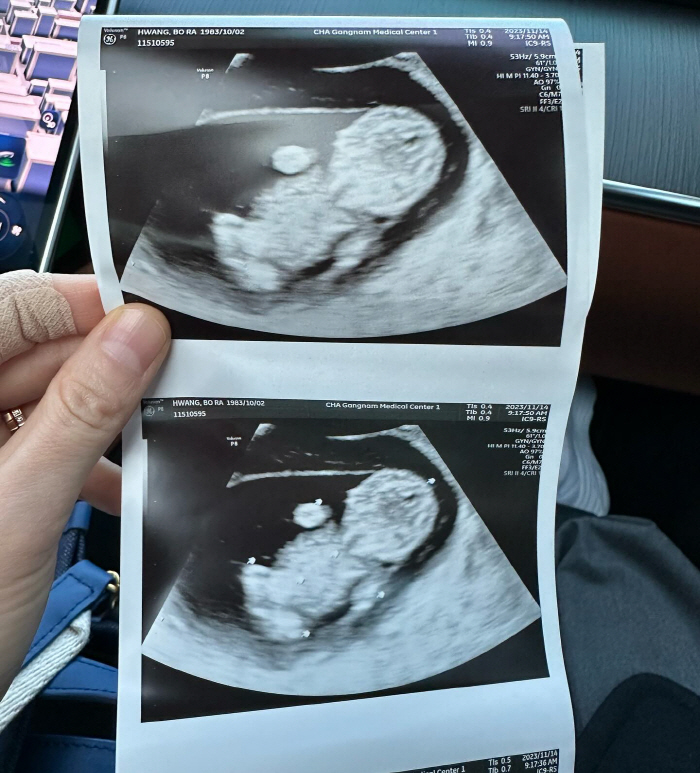

황보라는 "지금 착상한 시기다. 그 아이가 무난히 제 뱃속에 잘 자라서 저에게 아기 천사가 다가오길 바란다"며 "태명은 오덕이다. 다섯 가지의 덕을 가지고 태어난 아기이길 바란다는 뜻이다"며 간절하게 소원을 빌었다.

한편 황보라는 지난 19일 자신의 SNS를 통해 "결혼한 지 딱 일 년이 되었는데 저희 부부에게 하나님께서 아기천사를 주셨다"며 임신 사실을 직접 알려 많은 이들로부터 축하를 받았다. 이어 황보라는 "나의 모든 것을 아낌없이 주고만 싶고 모든 것을 다 주어도 아깝지않은 이런 사랑을 처음 느껴본다"며 "엄마가 된다는 걸 알기 전까지 누군가를 내 몸과 같이 사랑한다는 것을 실제 한 몸이 되어 가르쳐 준 나의 작은 아기천사 우리 오덕이 엄마에게 와줘서 고마워"라고 덧붙여 눈길을 끌었다.